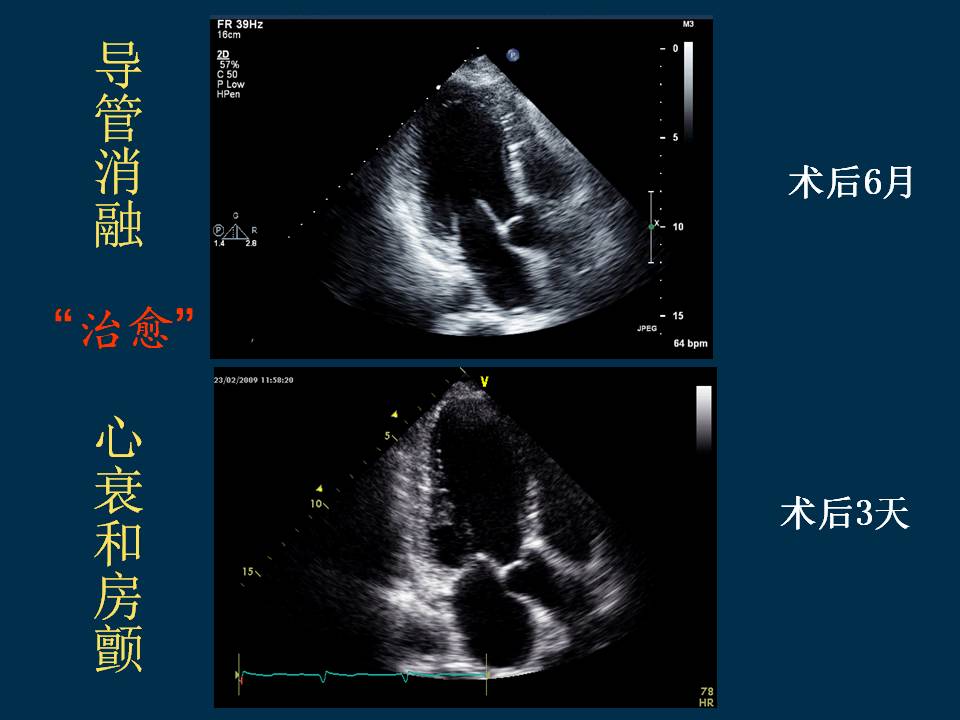

房颤导管消融远期随访的大型前瞻性研究